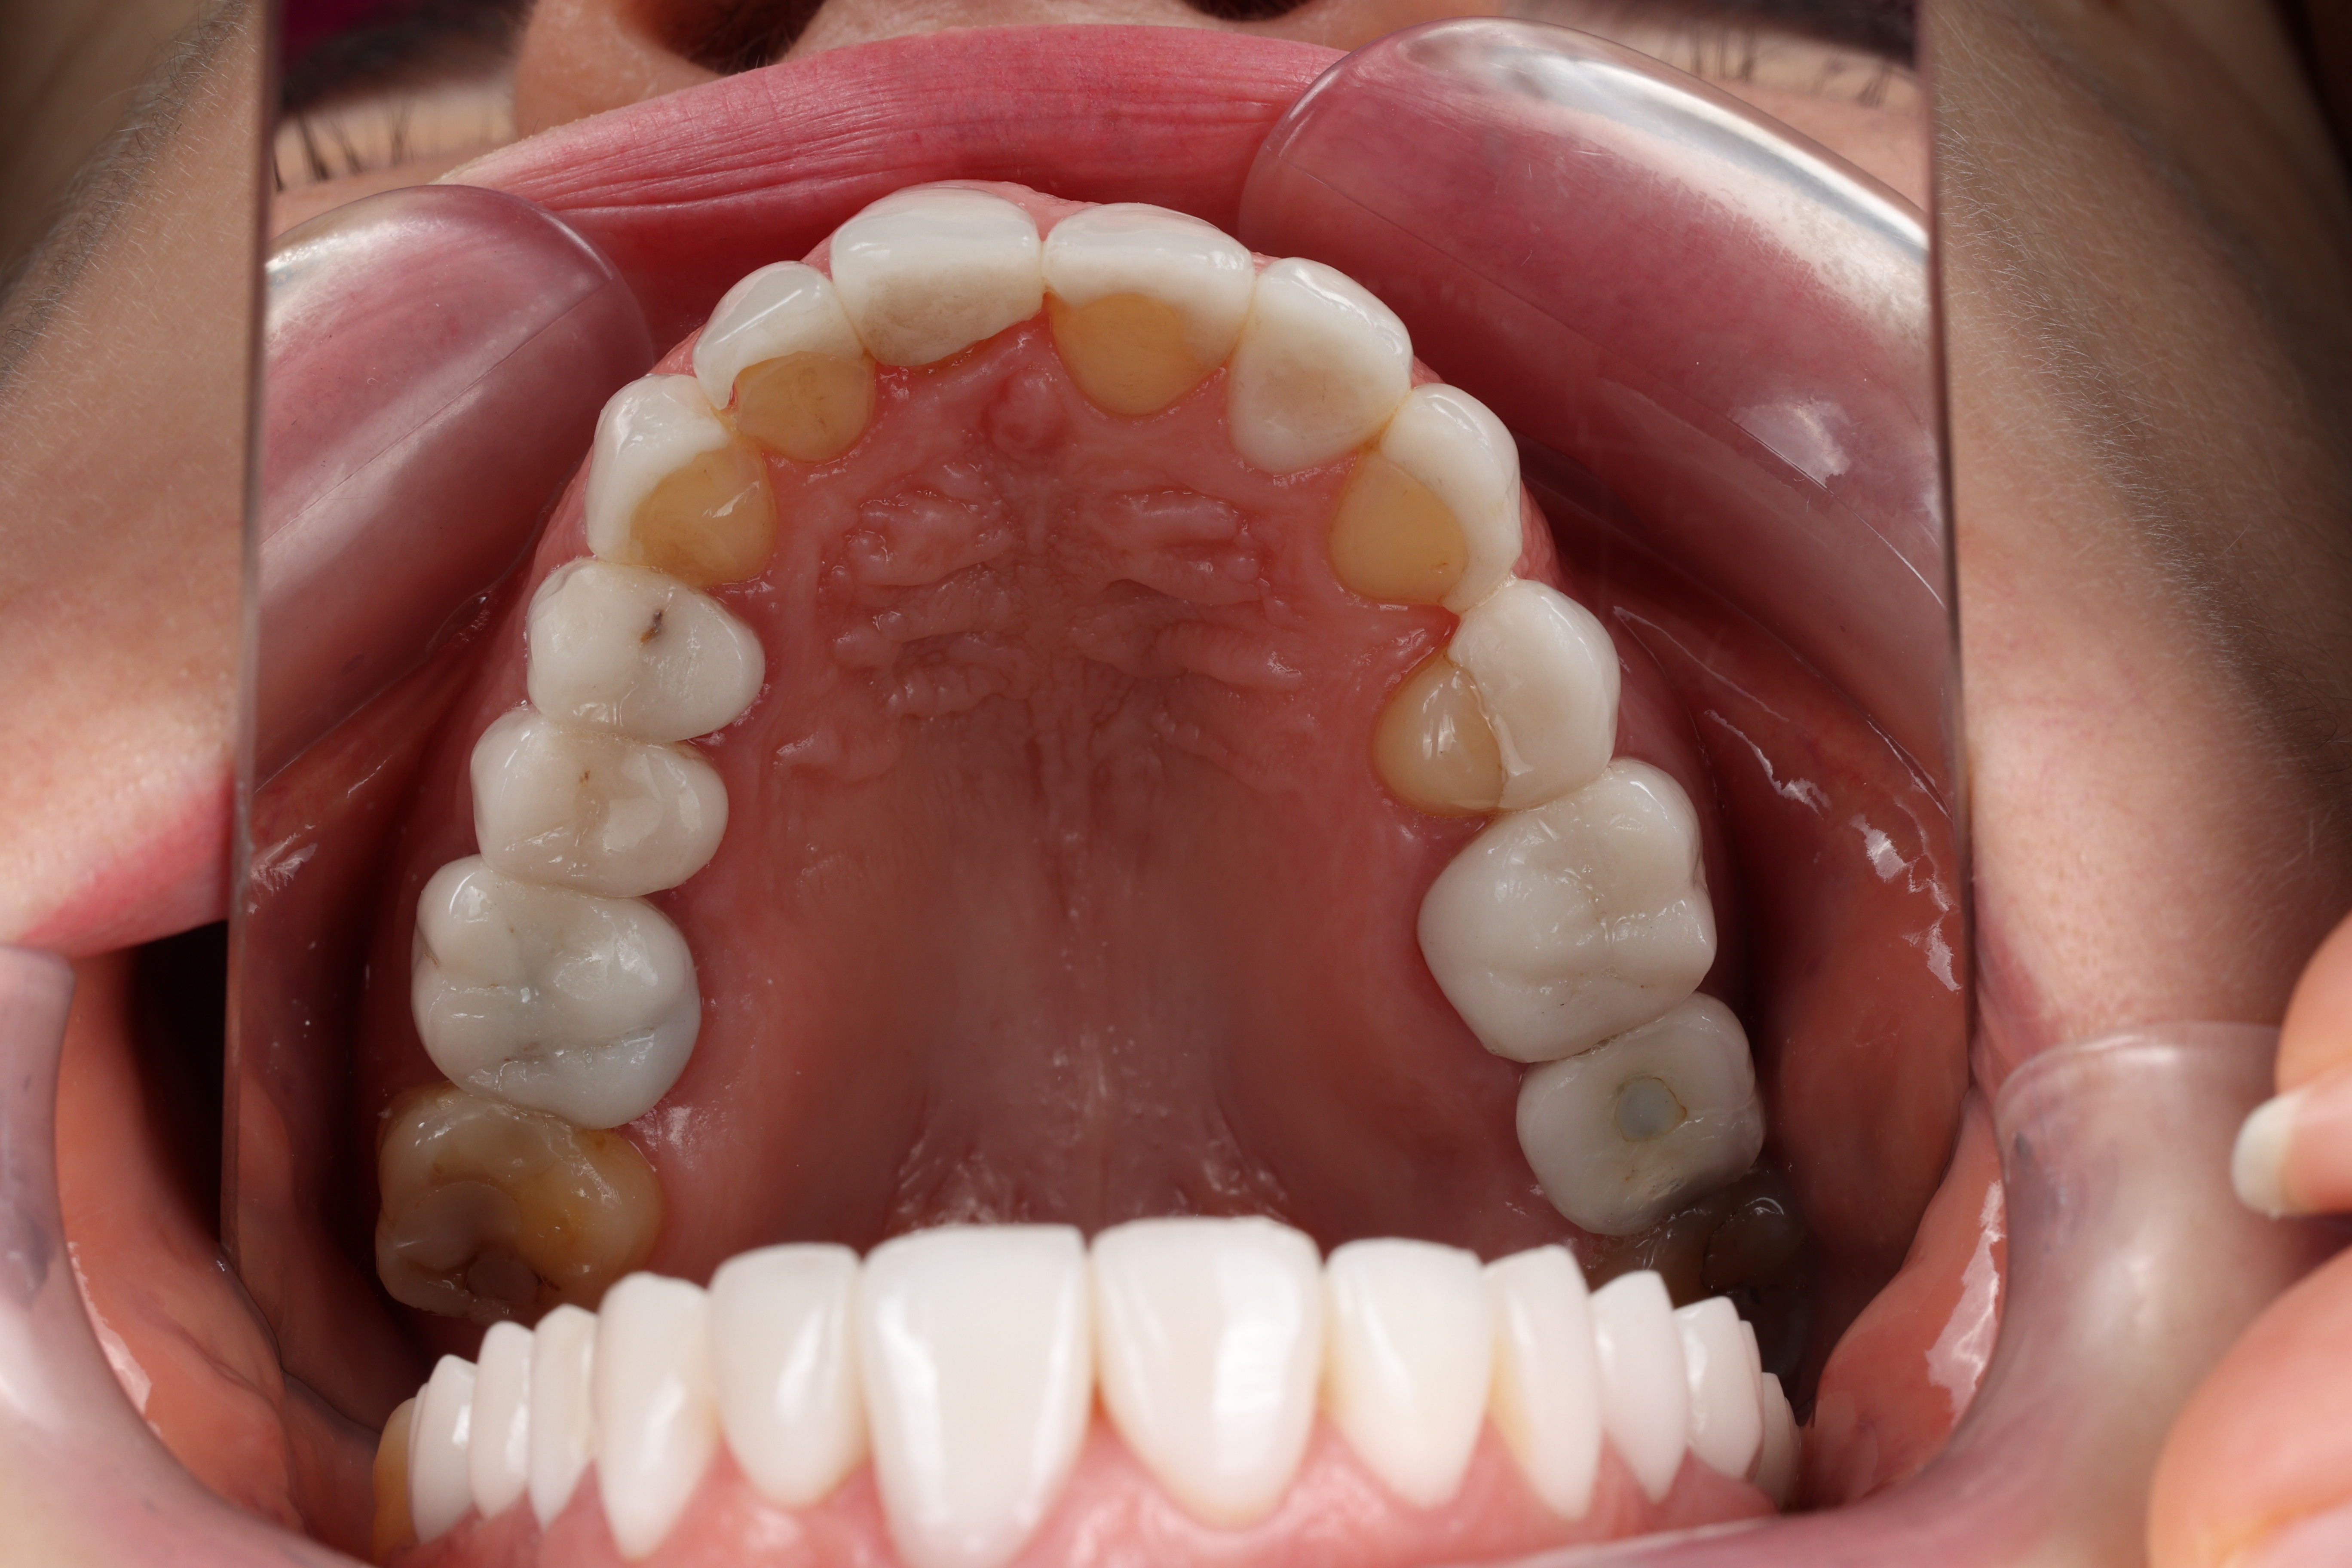

❗ First, I saw that her teeth had been overly prepared — with nearly all the enamel removed. Veneers should be bonded to enamel for strength and durability. This was a critical error.

⚠️ Second, there had been no functional analysis. Her bite was unbalanced, ceramics were fracturing, and muscles were overloaded.

📷 We completed a photo protocol, designed a physiological bite, and gave her temporaries to adapt with. Then we created custom Emax veneers and crowns, perfectly tailored to her function and aesthetics.

17 feldspathic veneers and 7 Emax crowns — 112,000 AED